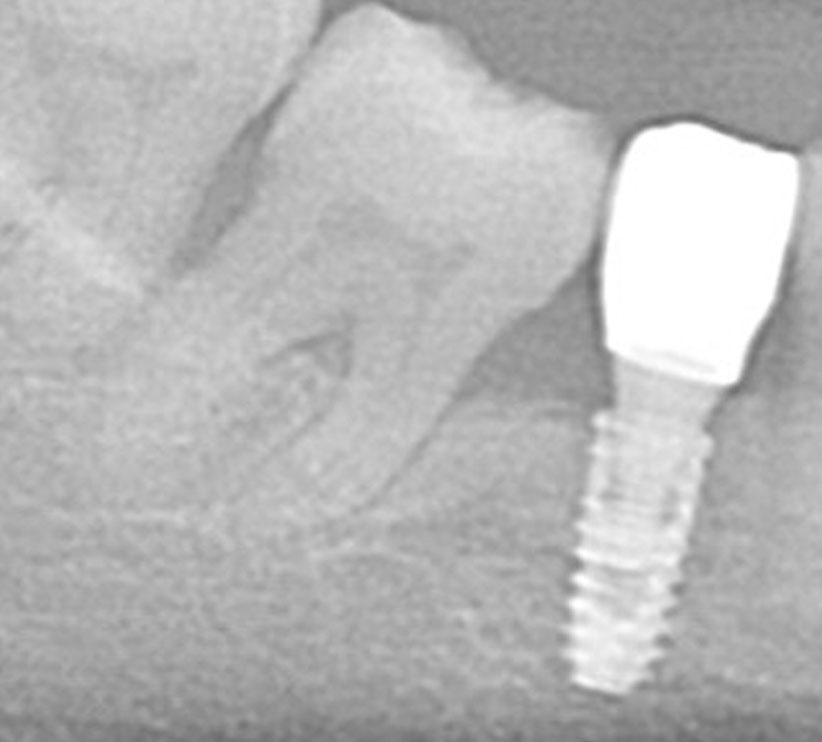

Before

After

| 主訴 | 歯茎が痛い、ムズムズする |

| 年齢 | 50代 |

| 費用 | 88,000円(税込) |

| 治療期間 | 2回 |

| リスク・副作用 | 外科手術が必要、自由診療のため費用がかかる |